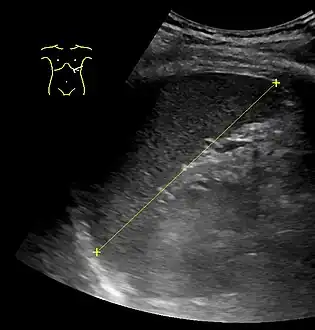

Measurements

90% confidence interval of spleen length by abdominal ultrasonography by height of the person[11]

HeightSpleen length

WomenMen

155–159 cm6.4–12 cm

160–164 cm7.4–12.2 cm8.9–11.3 cm

165–169 cm7.5–11.9 cm8.5–12.5 cm

170–174 cm8.3–13.0 cm8.6–13.1 cm

175–179 cm8.1–12.3 cm8.6–13.4 cm

180–184 cm9.3–13.4 cm

185–189 cm9.3–13.6 cm

190–194 cm9.7–14.3 cm

195–199 cm10.2–14.4 cm

The spleen, in healthy adult humans, is approximately 7 to 14 centimetres (3 to 5+12 in) in length.

An easy way to remember the anatomy of the spleen is the 1×3×5×7×9×10×11 rule. The spleen is 1 by 3 by 5 inches (3 by 8 by 13 cm), weighs approximately 7 oz (200 g), and lies between the 9th and 11th ribs on the left-hand side and along the axis of the 10th rib. The weight varies between 1 oz (28 g) and 8 oz (230 g) (standard reference range),[12] correlating mainly to height, body weight and degree of acute congestion but not to sex or age.[13]